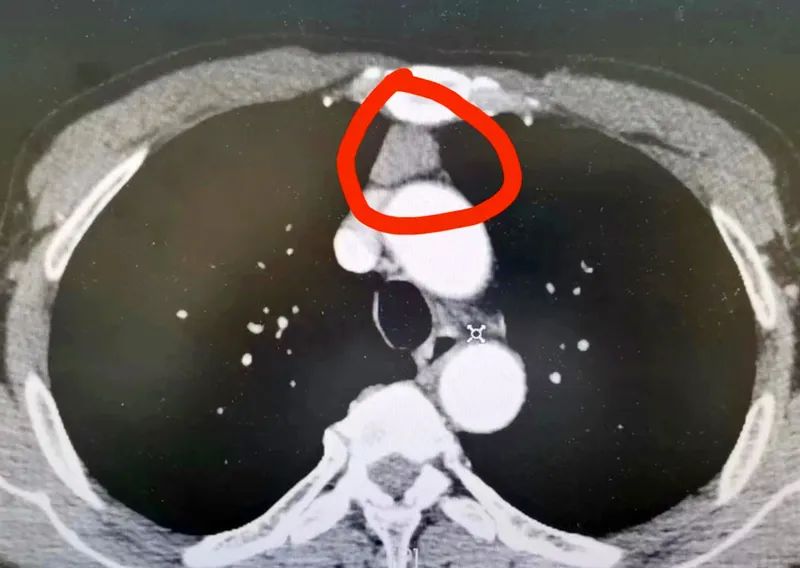

在住院行CT檢查時(shí)

發(fā)現(xiàn)體內(nèi)有一個(gè)

雞蛋大小的腫物

長在胸腔內(nèi)

前縱膈、心臟邊緣

經(jīng)綜合分析楊大哥的影像資料

吳主任考慮該病灶為胸腺瘤

不排除為惡性腫瘤

腫物附近為

心臟及胸腔大血管

神經(jīng)等器官、組織